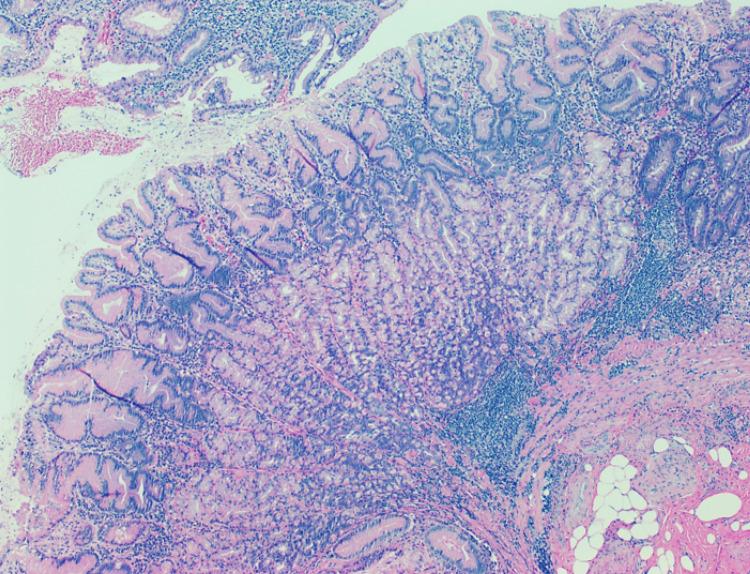

Introduction The intraoperative biopsy of a perforated gastric ulcer is a common practice; however, it may prove to be therapeutically futile, as an upper gastrointestinal endoscopy (UGE) is indicated regardless of the result. Objective To evaluate the histology of the perforated gastric ulcer biopsy (PGUB) and its effect on the subsequent clinical course. Methods A retrospective study (May 2017 to June 2024) of patients diagnosed with perforated gastric ulcer (K251 and K255 - ICD-10), with a review of medical records in the Medical Support System, was conducted. The histology of the PGUB, the performance of UGE, the degree of concordance between the histology of both, and the potential waiver of UGE were evaluated. Informed consent was waived, as this is an observational study without any interference with clinical conduct. Results During the evaluation period, 21 patients underwent PGUB, and 19 patients had a benign histological result; one patient was diagnosed with high-grade non-Hodgkin lymphoma, and one patient had gastric adenocarcinoma. In the following period, 10 patients underwent UGE, and in none of them did the histological diagnosis change. Of the remaining 11 patients who did not undergo UGE, five died, one was lost to follow-up, three are awaiting the procedure, and only two did not undergo the endoscopic exam. Conclusion The intraoperative biopsy of a perforated gastric ulcer is possibly futile, as it does not alter the clinical course. Regardless of the histological result obtained, a UGE is requested.

引言 胃溃疡穿孔的术中活检是一种常见的操作;然而,它可能被证明在治疗上是徒劳的,因为无论结果如何都需要进行上消化道内镜检查(UGE)。目的 评估胃溃疡穿孔活检(PGUB)的组织学及其对后续临床病程的影响。方法 对2017年5月至2024年6月诊断为胃溃疡穿孔(国际疾病分类第十版中的K251和K255)的患者进行回顾性研究,查阅医疗支持系统中的病历。评估PGUB的组织学、UGE的执行情况、两者组织学之间的一致性程度以及UGE的潜在豁免情况。由于这是一项不干扰临床行为的观察性研究,因此无需获得知情同意。结果 在评估期间,21例患者接受了PGUB,19例患者组织学结果为良性;1例患者被诊断为高级别非霍奇金淋巴瘤,1例患者患有胃腺癌。在接下来的时期,10例患者接受了UGE,他们的组织学诊断均未改变。其余11例未接受UGE的患者中,5例死亡,1例失访,3例正在等待该检查,只有2例未接受内镜检查。结论 胃溃疡穿孔的术中活检可能是徒劳的,因为它不会改变临床病程。无论获得的组织学结果如何,都需要进行UGE。